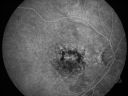

79-year-old woman was seen in the office on 12/22/2009. She has noticed, since the YAG capsulotomy in November of 2009, distortion in the right eye. Part of what she saw were fluffy blue clouds but sometimes there are gray clouds and then she notices that lines are wavy. She does not notice it as much on the Amsler grid as she does on her blinds. This is all in the right eye. The left eye continues to see fine. She does have health problems, including atrial fibrillation for which she takes Coumadin. She also notices pain around the right eye when she bends down VISUAL ACUITY: Vision OD is 20/30, OS is 20/20. IOP: OD 14, OS 13. AMSLER GRID: Right eye has central metamorphopsia. The left eye is normal. SLIT LAMP EXAM: She does have a posterior chamber intraocular lens in good position in both eyes with open capsules with 2+ vitreous debris. EXTENDED OPHTHALMOSCOPY: OD: Vertical C/D ratio is 0.4. There is no posterior vitreous separation. There are hyperpigmented spots superior to the fovea. The fovea is slightly atrophic. OS: Vertical C/D ratio is 0.4. There is no posterior vitreous separation. There are hyperpigmented spots primarily superior to the fovea. There is no intraretinal or subretinal fluid. OCT SCAN: The OCT scan confirms both macula to be dry. PHOTOGRAPHS: Photos confirm clinical findings. FLUORESCEIN ANGIOGRAPHY: There is increase in hyperfluorescence and hypofluorescence in the macula of both eyes. In the right eye there is substantially more hyperfluorescence centrally where the atrophy is. IMPRESSION: 1. NONGEOGRAPHIC PIGMENTED EPITHELIAL ATROPHY – RIGHT EYE 2. PATTERN DYSTROPHY-TYPE MACULAR DEGENERATION – BOTH EYES 3. RECENT AMSLER GRID CHANGE – RIGHT EYE 4. PAIN AROUND RIGHT EYE DISCUSSION: I explained to the patient that both maculae have pattern dystrophy-type dry age-related macular degeneration. I do not see any sign of bleeding or fluid or anything acute that needs attention.

Patterned Pigment Dystrophy of the Fovea 79 YO Woman VA 20/20 Right 20/30 Left787 views00000